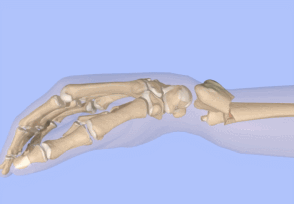

3用手触摸骨折断端,

这个时候有时候会有背侧皮质坎墩的情况

这个时候需要再斜向上牵引一下,

然后用拇指以断端为中心进行一个掌屈

4复位之后需要进行X线的检查,

如果满意的话可以进行石膏的固定